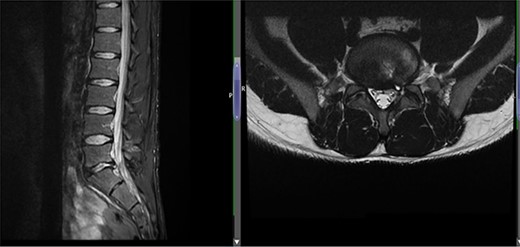

(A) Case 3—an early MRI demonstrates at L5/S1 level moderate diffuse disc bulge is seen with early bilateral facet joint degenerative changes; there is irritation of the L5 nerve roots bilaterally, and at L5/S1 level moderate left posterolateral disc bulge is seen irritating the S1 nerve roots bilaterally left more than right, and bilateral facet joint degenerative changes also noted at this level, and (B) case 3—a later MRI, the cystic changes noted at the L4-L5 level which clearly shows a connection with the intervertebral disc.